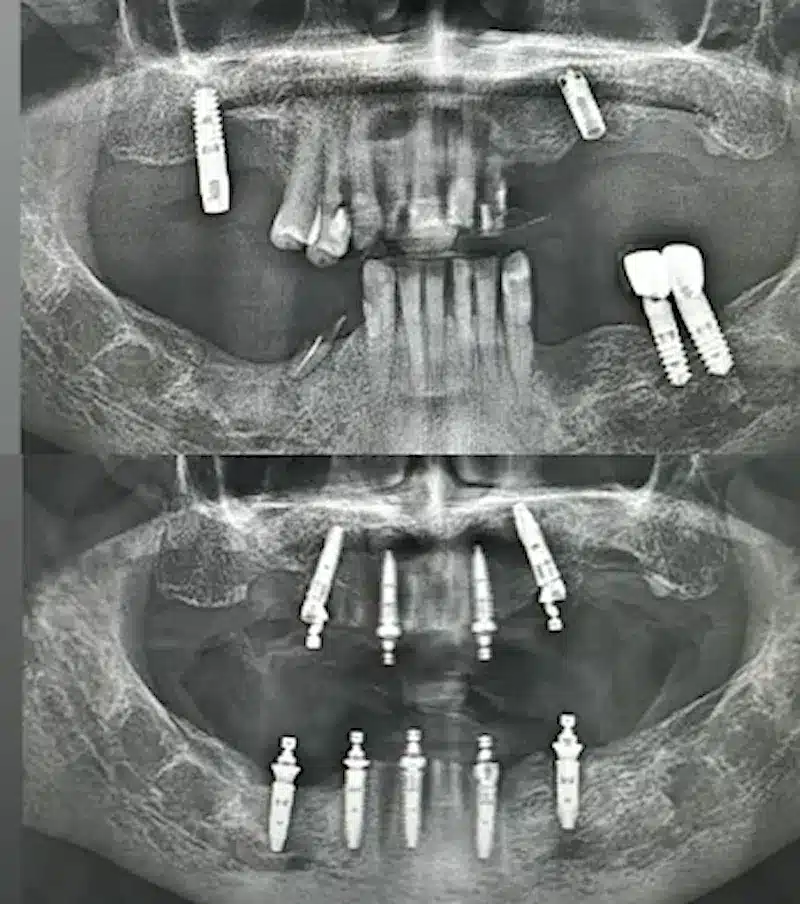

Dr. Seden Aksu is a specialist in modern implantology and surgical dentistry with extensive experience in the management of complex clinical cases. In her practice, she applies comprehensive surgical planning, minimally invasive techniques, and advanced regenerative technologies aimed at restoring both the function of the dentoalveolar system and the aesthetics of the smile. Dr. Aksu has significant experience in performing implant procedures, bone augmentation, and periodontal surgery, including the treatment of patients with severe bone loss. The primary goal of her work is to achieve stable, long-term outcomes in implant rehabilitation and the restoration of oral tissue health.